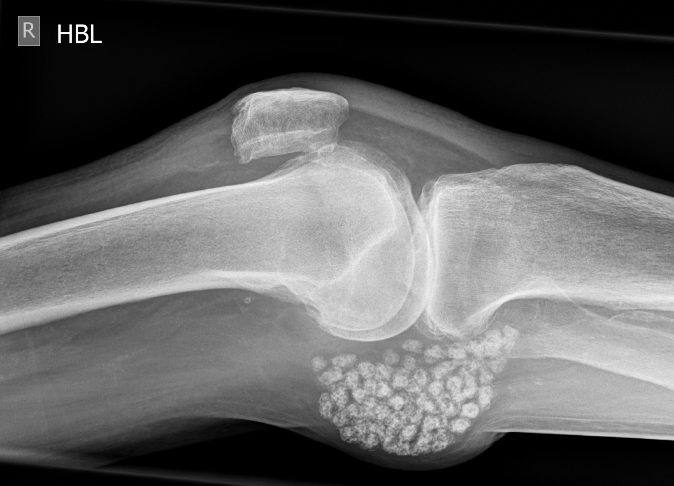

3. Synovial osteochondromatosis in a Baker's cyst